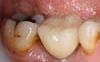

Image 06

Completed cerec crown.